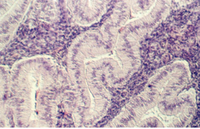

Slide 86 shows a uterus in the proliferative phase. The endometrium is illustrated in the photograph below. Note that the cells are low columnar to high columnar. The glands are relatively straight with a narrow lumina. Outside the glands is the highly cellular lamina propria. The following photos illustrate the proliferative phase with higher magnifications.

After ovulation, the uterine lining becomes more tortuous. The lining is now under the control of progesterone. This steroid hormone stimulates the lining to secrete material that may help nourish both sperm and a potential pregnancy. The glands expand and the lumina are wide and contain products of secretion. The glandular epithelium may be characterized by a droplet of secretory material under the nucleus (near the base) about 2 days after ovulation (day 16). Then, the secretory products move more towards the lumen. Slide 87 shows the Secretory phase of the uterine lining. Note the sections showing coiled or tortuous glands and the dense lamina propria.